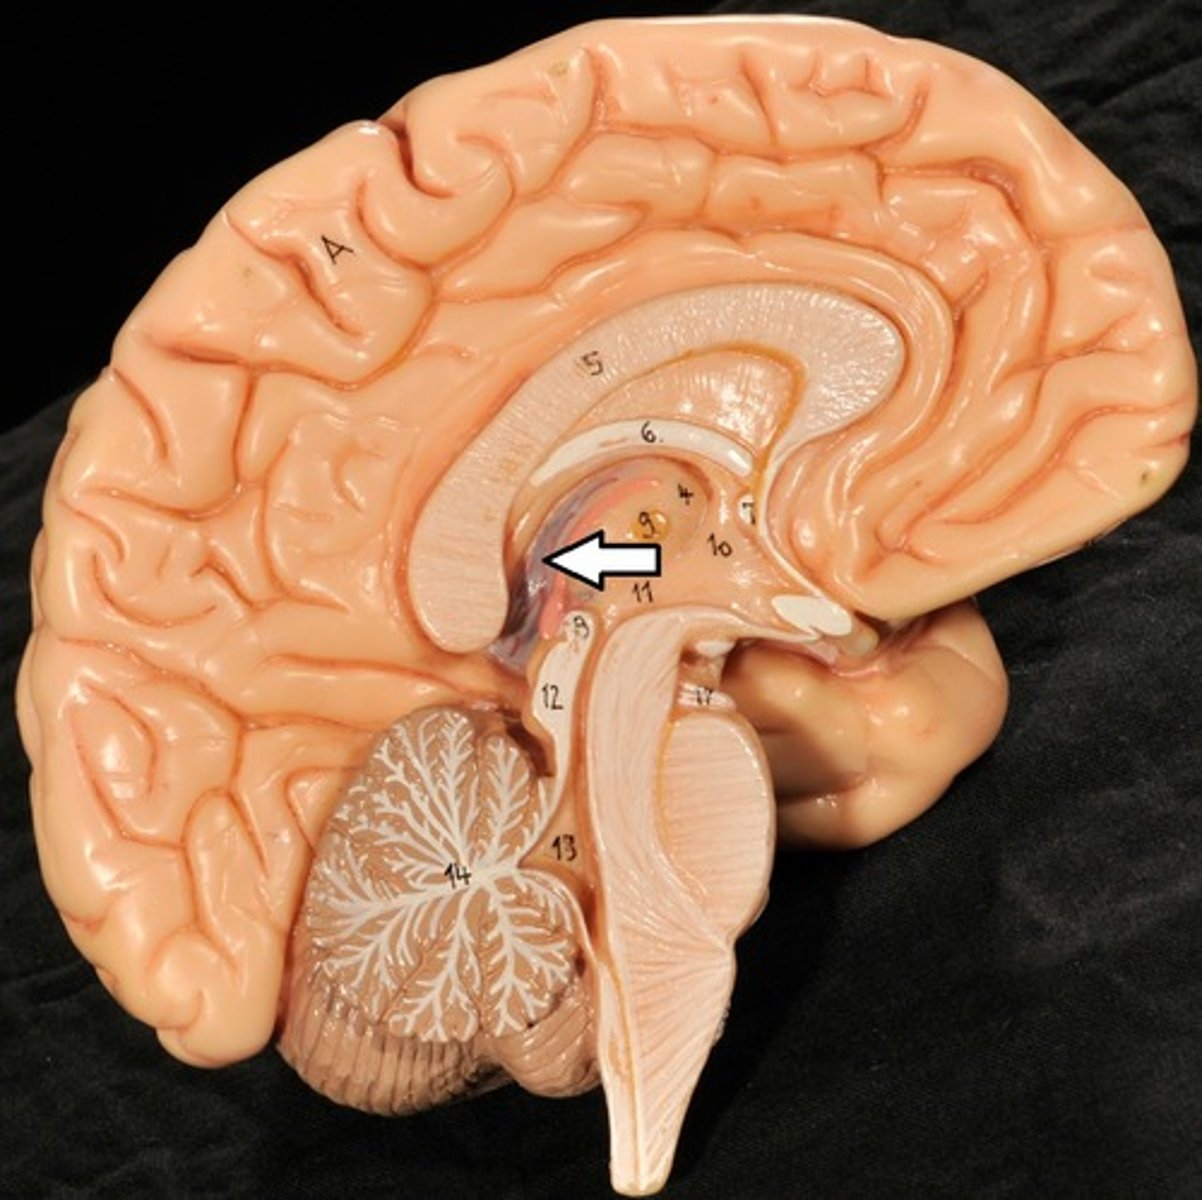

Ventricles

1) Right & left lateral ventricles:

-Anterior, Posterior & inferior horns

2) 3rd Ventricle, Cerebral aqueduct, 4th ventricles

4) Apertures (Narrow openings) into subarachnoid space of spinal cord

Anterior Horns

Posterior Horns

Inferior Horns

3rd Ventricle

4th Ventricle